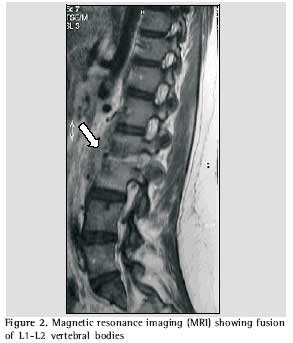

As her condition worsened, leading to difficulty in moving about, she was advised to seek medical assistance at a neurosurgery outpatient clinic, where she was submitted to lumbosacral spine computed tomography, magnetic resonance imaging, chest X-ray, biopsy of the affected site and blood count (including determination of erythrocyte sedimentation rate). Computed tomography revealed irregularity and reduction of the articular space between L2 and L3, concomitant with sclerosis of the corresponding vertebral bodies, as well as fracture in L2. The vertebral disk between L5 and S1 presented a slight protrusion, without causing significant intrarachidian repercussions. The findings suggested the possibility of an inflammatory or infectious process, or both, involving the L2 and L3 vertebral bodies, as well as the corresponding intersomatic disk (Figure 1). Magnetic resonance revealed reduction of the L2/L3 disk space and cold abscess in the corresponding area, which reinforced the possibility of a spondylodiscitis-like process (Figures 2 and 3).

Magnetic resonance is the most sensitive and most specific method for differentiating the nature of the vertebral collapses, in addition to showing early alterations(9,18,19) that aid in diagnosing tuberculous spondylitis(20). However, it may produce similar imaging results in cases of vertebral neoplasia and infection by pyogenic bacteria(9, 21).

In pyogenic infections, reduction of the intervertebral space is atypical(20,22). Nevertheless, for our patient, the imaging revealed intervertebral reduction concomitant with involvement of consecutive vertebrae, both of which are considered characteristic of tuberculous spondylitis(9).